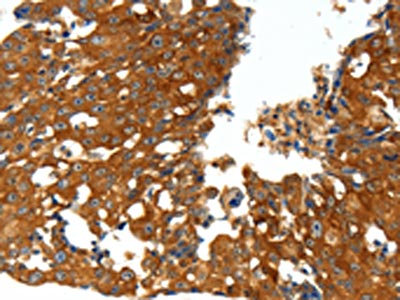

The image on the left is immunohistochemistry of paraffin-embedded Human breast cancer tissue using CSB-PA968386(CXCL12 Antibody) at dilution 1/20, on the right is treated with synthetic peptide. (Original magnification: ×200)

The image on the left is immunohistochemistry of paraffin-embedded Human ovarian cancer tissue using CSB-PA968386(CXCL12 Antibody) at dilution 1/20, on the right is treated with synthetic peptide. (Original magnification: ×200)